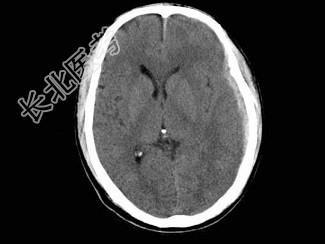

- 单项选择题男,38岁, 外伤后半个月,行CT复查如图, 最可能的诊断为 ( )

A、脑出血

B、硬膜外血肿

C、脑萎缩

D、脑挫裂伤

E、亚急性硬膜下血肿